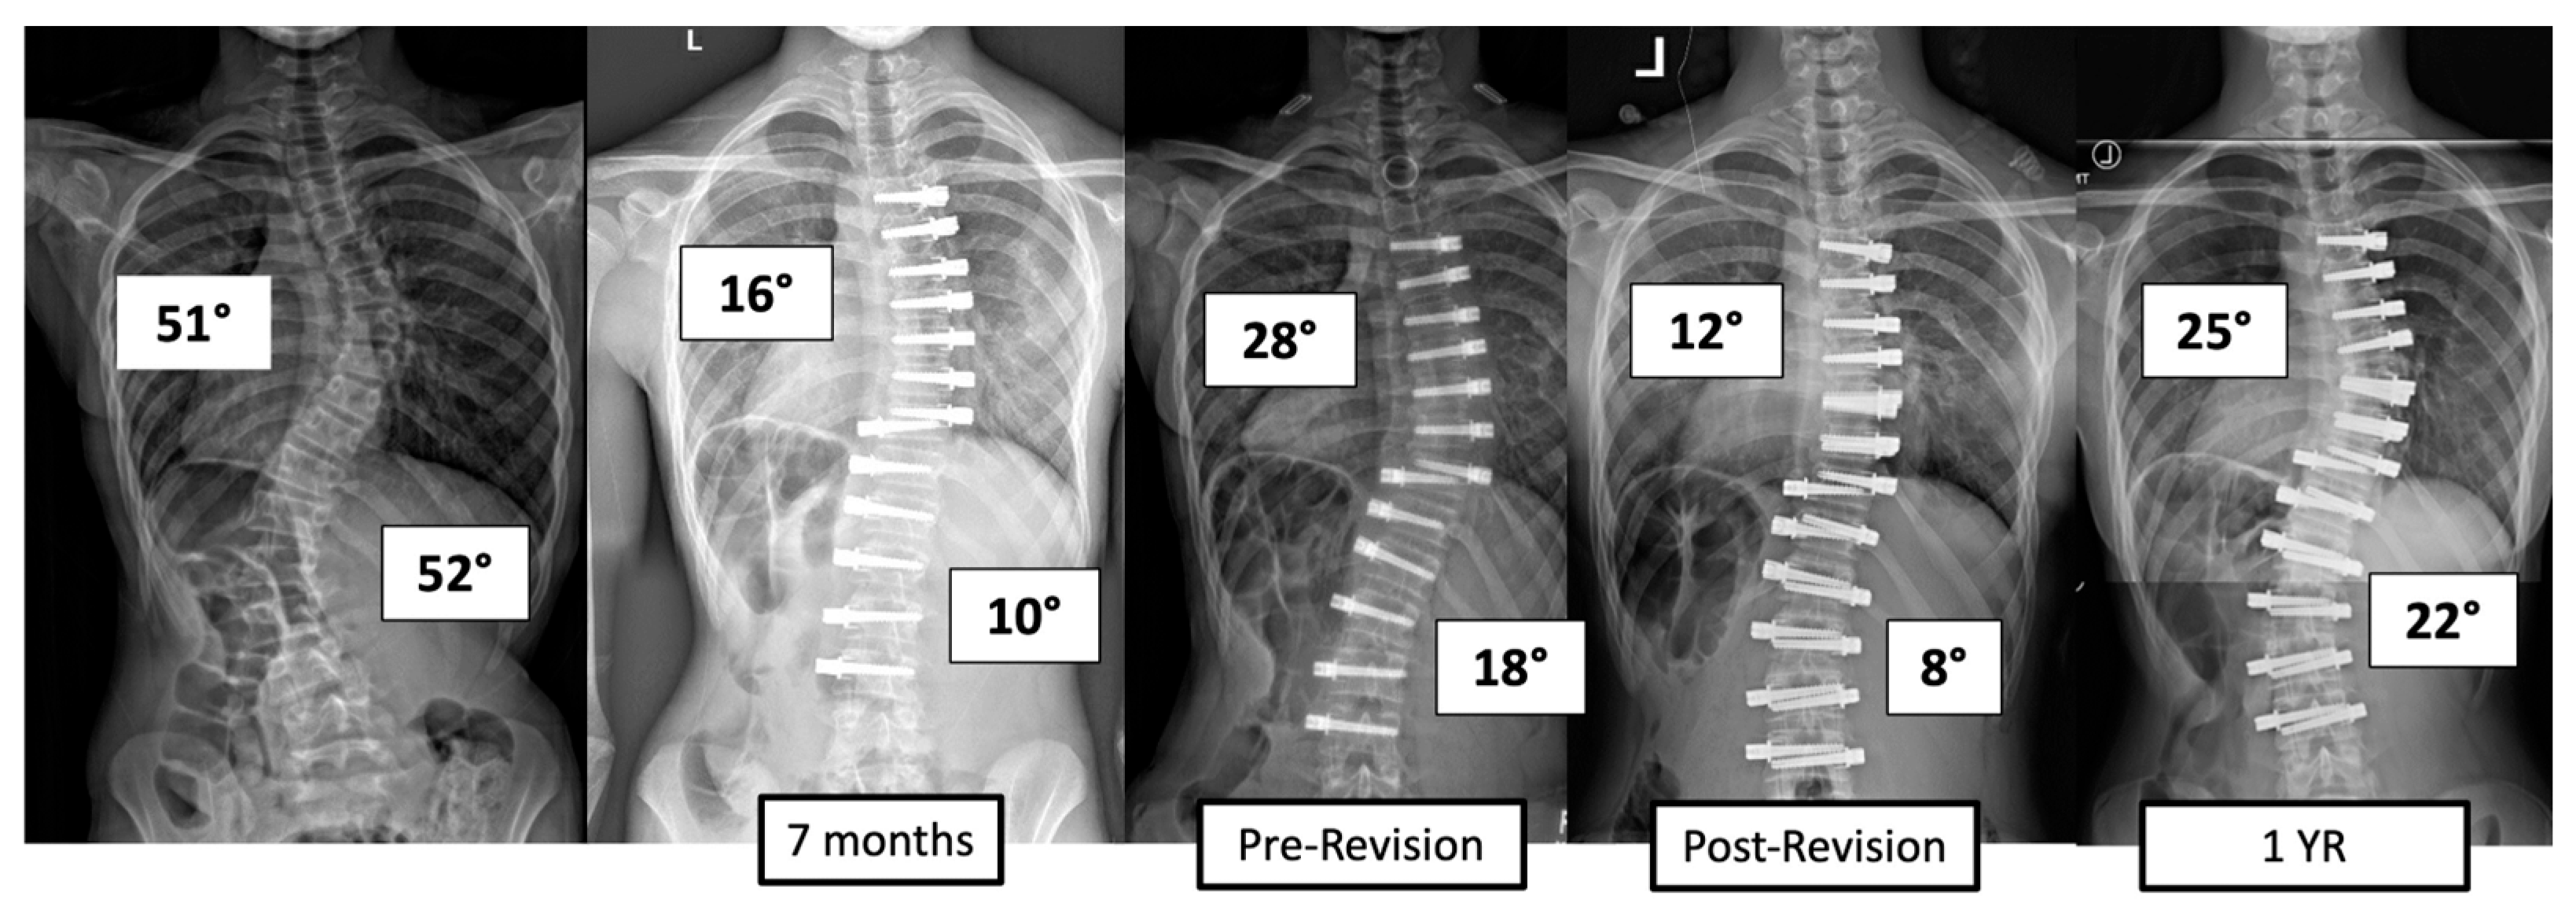

There were four major complications (10.8%), including one readmission and three patients who required re-operation. Patient 1 underwent re-operation due to radiculopathy caused by a screw tip impinging on a nerve root in a lumbar foramen requiring screw revision and replacement of the tether. At 3 years post operation, they have a broken tether at one level, but no further revision is needed. Patient 2 had progression of a previously uninstrumented thoracic minor curve which progressed following lumbar tether breakage. This was revised with fusion of the previously untreated thoracic curvature and the addition of a second row of screws and second tether for the thoracolumbar construct (Figure 3). Patient 3 had overcorrection of the thoracolumbar curvature and adding on of the thoracic. As a result, the tether was released in the thoracic region and the thoracolumbar tether was revised (Figure 4). One patient (3%) required readmission due to an inability to tolerate post-operative pain medication. During admission, pain was controlled, and they were discharged without sequela.

Figure 3.

This is a 13-year-old female who experienced progression of the thoracic curve following tether breakage in the lumbar spine. The patient was revised with fusion of the previously untreated thoracic curvature and addition of a second row of screws and second tether for the thoracolumbar construct.